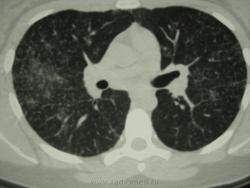

девушка 1985 г.р. дообследована после профилактической флюорографии, на КТ написали гистиоцитоз. Диагноз пока не подтвержден. Жалоб не предъявляет, курит в течение 8-9 лет. консультирована у фтизиатров, свою патологию они исключили.

На мой взгляд, выражены два компонента:

- преимущественно мономорфная диссеминации;

- интерстициальный компонент.

Но, КТ, по всей видимости, свидетельствует, именно, о диффузности процесса, с некоторым превалированием в отдельных отделах.